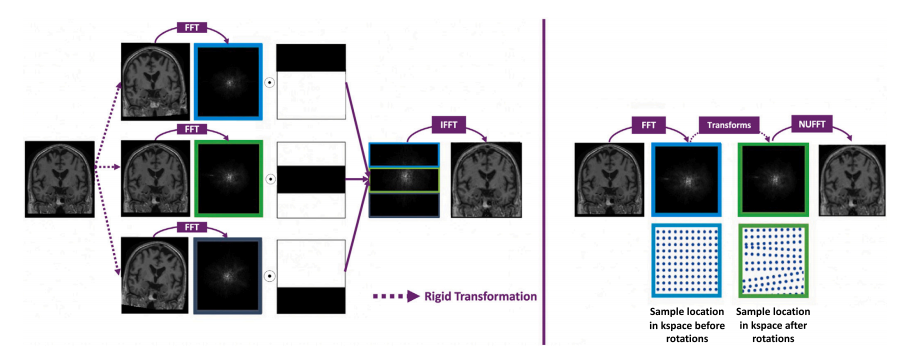

Fig. 1. Left: Image-based motion simulation. (1) 𝑁 𝑡 rigid transformations of the motion-free image are applied (here 𝑁 𝑡 = 2), (2) Fast Fourier transform (FFT) of the originaland 𝑁 𝑡 transformed images, (3) Concatenation of the 𝑁 𝑡 + 1 blocks to create a new k-space, (4) Inverse FFT (IFFT) to obtain the motion corrupted image. Right: k-space basedmotion simulation. (1) FFT of the motion-free image. (2) Transformation (rotation + translation) for each point of the time course. (3) Non uniform FFT (NUFFT) to reconstructthe corrupted image (because of the non uniform sample spacing due to the rotation in the k-space)

图1. 左:基于图像的运动模拟。(1) 对无运动伪影的图像应用 𝑁𝑡 次刚体变换(此处 𝑁𝑡 = 2),(2) 对原始图像和 𝑁𝑡 次变换后的图像进行快速傅里叶变换(FFT),(3) 将 𝑁𝑡 + 1 个块拼接以创建一个新的k空间,(4) 进行逆傅里叶变换(IFFT)以获得带有运动伪影的图像。右:基于k空间的运动模拟。(1) 对无运动伪影图像进行FFT,(2) 对时间序列中的每个点进行变换(旋转+平移),(3) 使用非均匀快速傅里叶变换(NUFFT)重建带有伪影的图像(由于k空间旋转导致的非均匀采样间隔)。